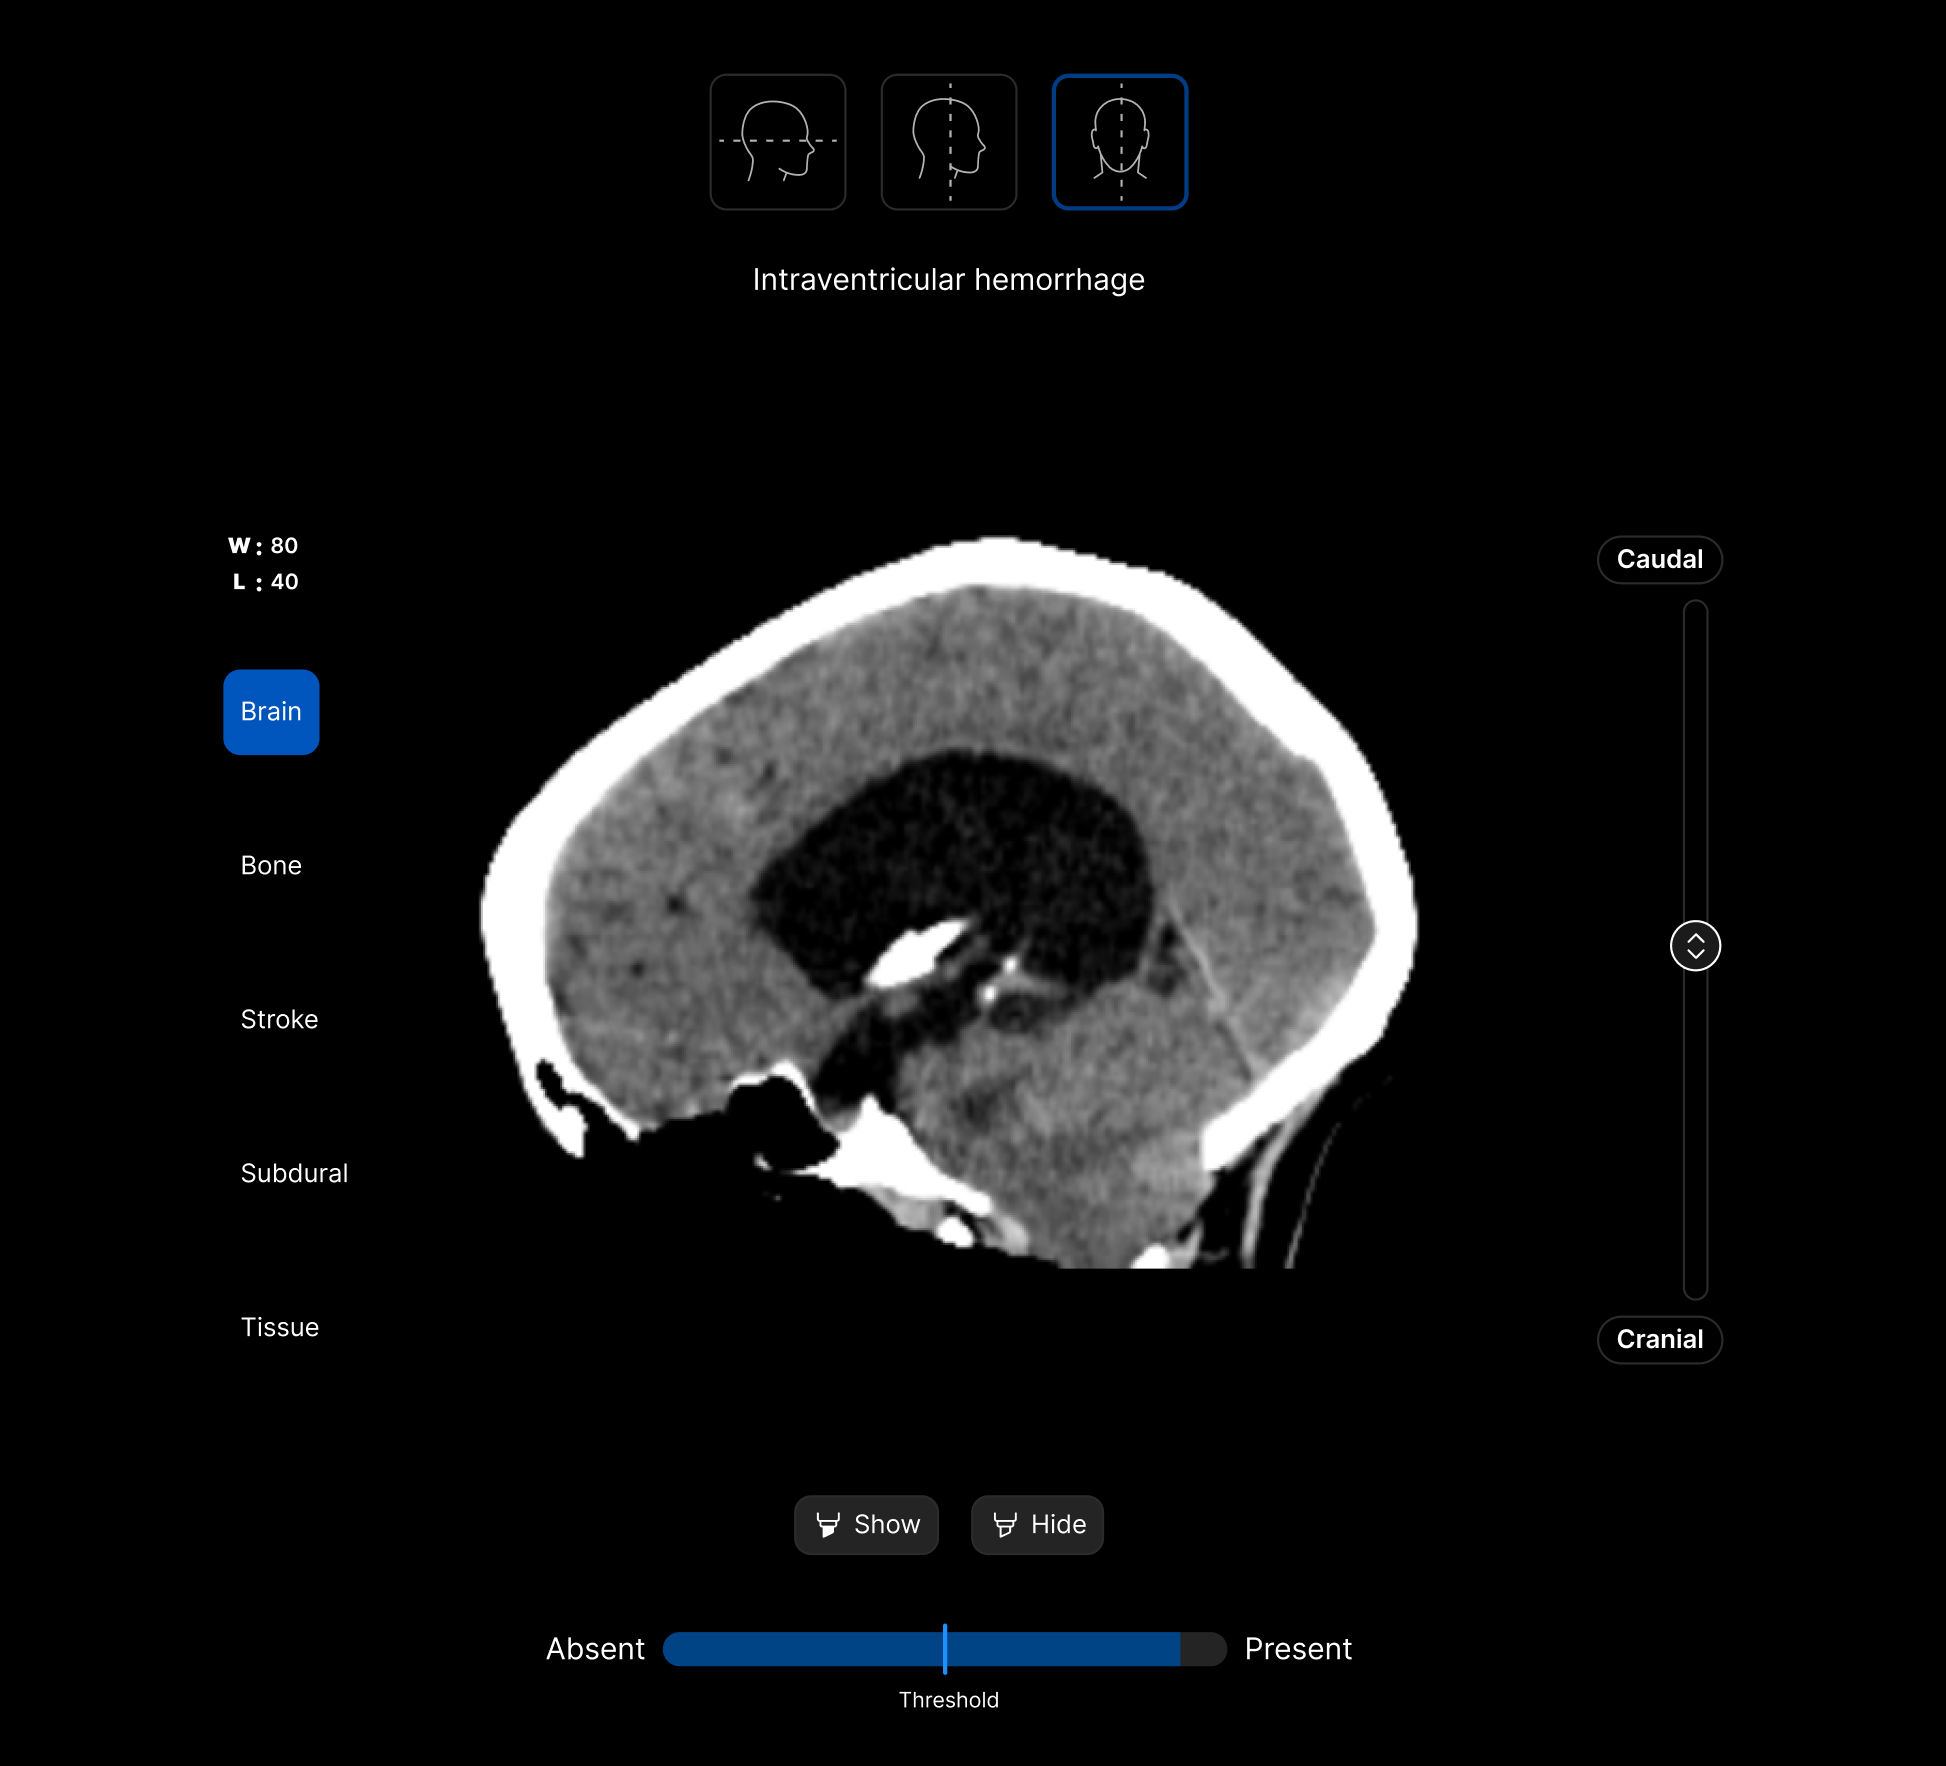

The UI integrates seamlessly with PACS/ RIS, displaying a resizable, no-click overlay window with findings and localisation.

Customisable features.

Customisable thresholds, for individual findings (to optimise for sensitivity / specificity) to tailor the workflow to your clinical setting or population.

Identifies up to 130 suspected head CT findings, grouped by urgency or other customisable criteria.

Coloured overlays on the image to quickly locate findings.

Explainable AI feature to improve AI interpretability and improve clinical decision-making.

AI analysis viewable on different head CT slices.

View the findings in sagittal, axial and coronal projections.

View findings within preset subdural, bone, brain, soft tissue and stroke views to provide additional context to the AI results.